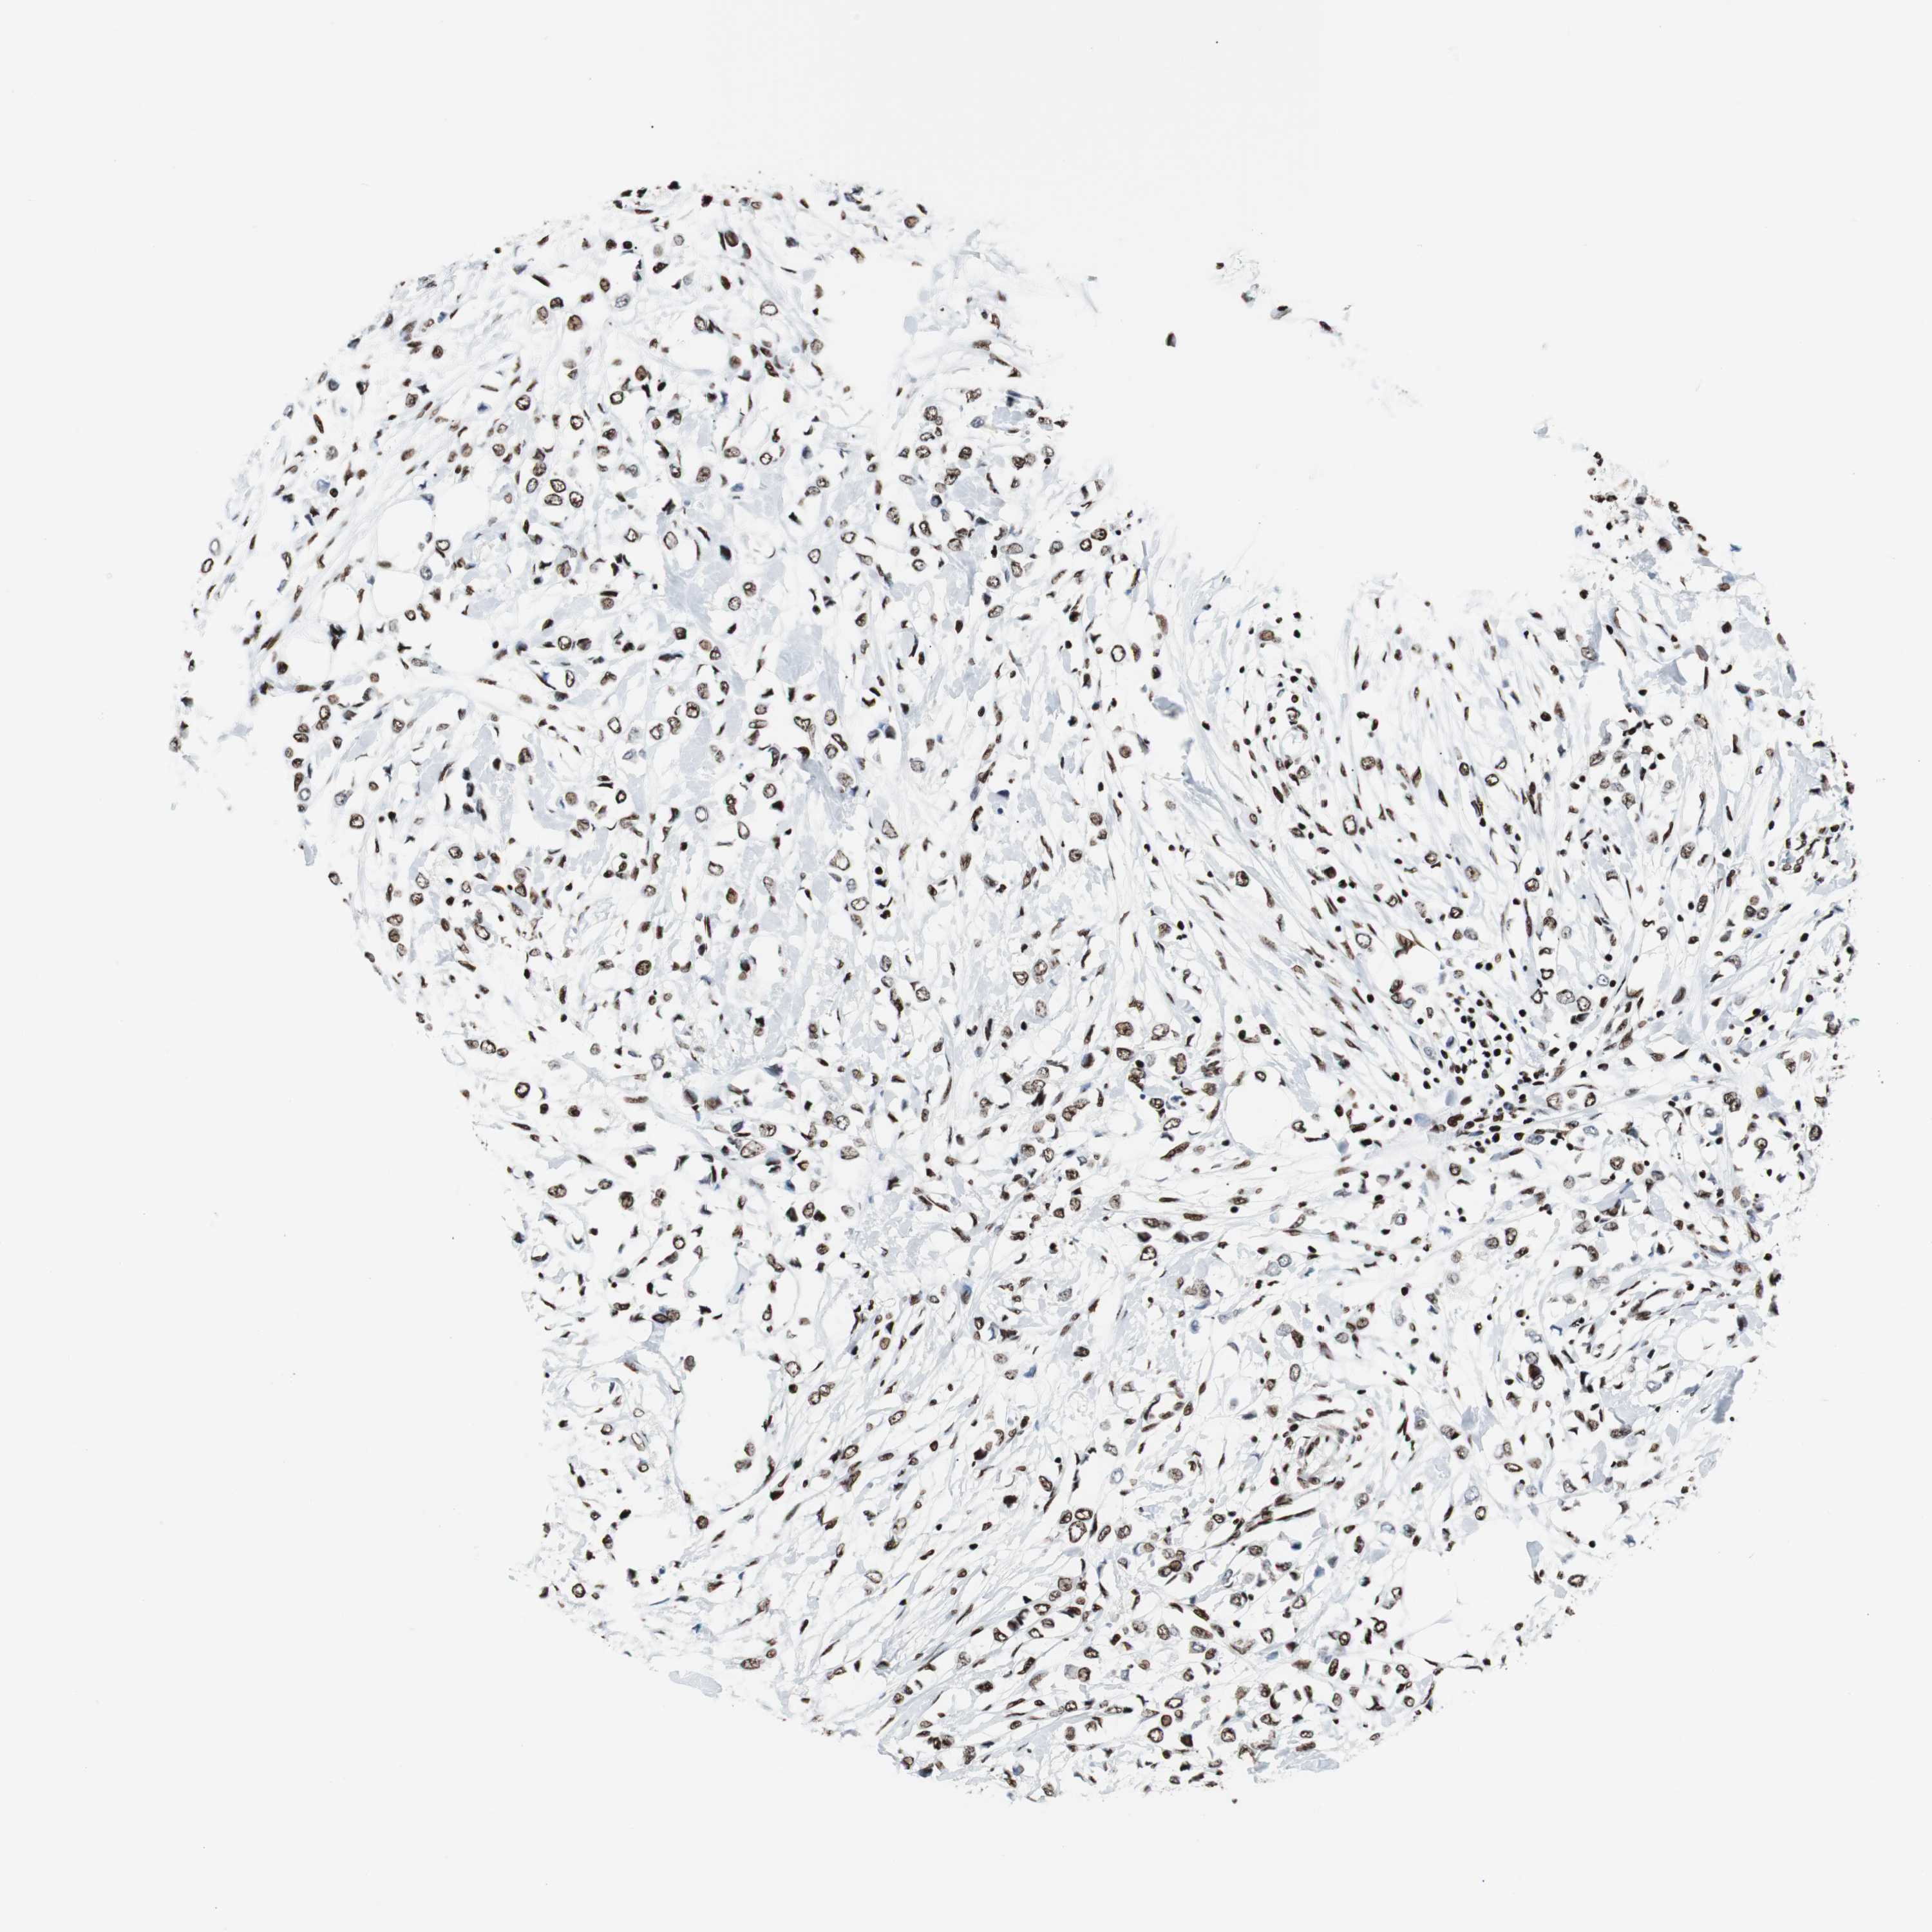

BRCA TCGA BRCA VALIDATION PROTEIN EXPRESSION